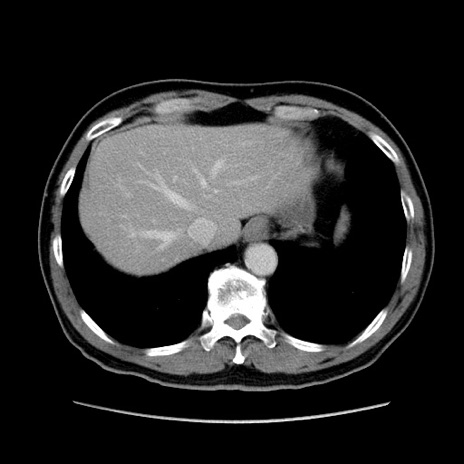

症例34(横断像)

【症例】60歳代 男性

【主訴】右鼠径部膨隆

【現病歴】1年程前より右鼠径部膨隆あり。自己にて還納可能だったため放置していた。3時間前より右鼠径部の脱出を認め、還納困難となり受診。

【身体所見】右鼠径部に小児頭大の膨隆あり。弾性硬であり、用手還納は困難。左鼠径部にも膨隆を認める。脱出はなし。